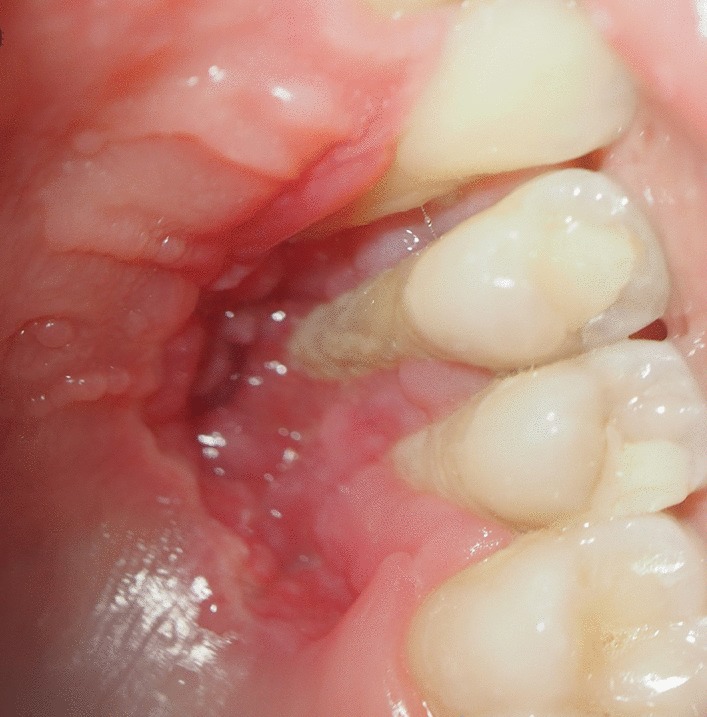

At 18 year old, a Caucasian female patient without any systemic diseases or drug use was presented for evaluation of gingival problems around her upper right premolar. Marginal periodontitis was diagnosed by her Dentist and the patient was referred to a Periodologist for root scaling. During the next two years, the patient was undergone perio-treatments under anti-inflammatory medications and had root canal treatment of her second premolar one year later. Biopsy of the lesion was not taken but the lesion was not gone but slowly progressed and therefore the patient was referred to a maxillofacial surgeon at our clinic. During her first consultation with the maxillofacial surgeon, the patient only complained about gingival recession in the palatal area of her upper-right-side teeth. The initial examination showed that the canine and both premolars had second-grade mobility (Fig. 1). The probing depth of teeth 13, 14, and 15 was < 3 mm on the buccal side and 5 mm at the palatal side as the palatal gingiva were recessed leaving exposed the fist premolar and canine and less the second premolar whose exposed root surface was covered with dental plaque. The patient’s jaw underwent 3D computed tomography, which revealed bone destruction in the defect area reaching the maxillary sinus, whose mucosa was locally thickened (Fig. 2). The condition of periodontium around other teeth was fine. The probing depth was < 3 mm around all other teeth. The chronic long-term lesion, with its unknown cause and unusual localization (defect in the palate side, while the marginal buccal surface bone was uninjured), caused confusion to the Oral Surgeon as the clinical findings were not characteristic of oncological tumors: such as the absence of induration of adjacent soft tissues, the boundaries were clearly visible, and the unpleasant smell characteristic of tissue collapse was not detected from the lesion. Moreover, no regional lymph nodes were palpable, and none of the patient’s close relatives were having similar lesions.

Fig. 1.

Clinical photograph of defect in maxilla